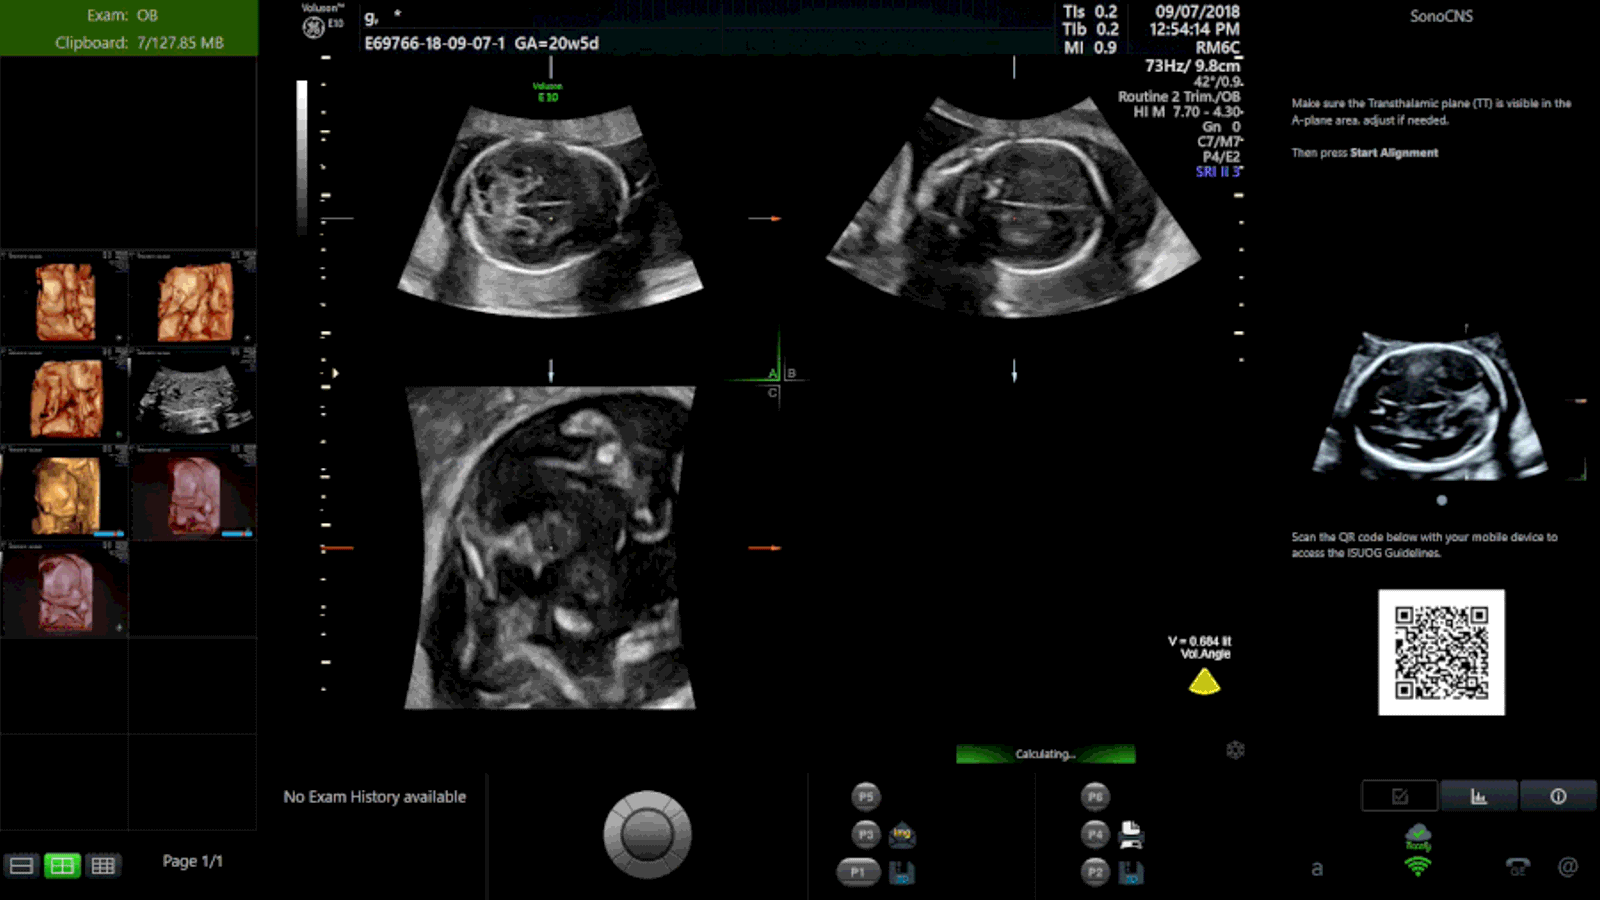

AI & AutomationSonoLyst uses deep learning to recognize standard fetal anatomical views during OB/GYN ultrasound exams. As the sonographer scans, the system identifies which anatomical structures and imaging planes have been captured and which remain outstanding. This real-time checklist approach helps ensure exam completeness, particularly for second-trimester anatomy surveys where missing a required view can mean recalling the patient. SonoLyst runs on GE Voluson systems and is trained on OB/GYN-specific datasets covering fetal brain, face, spine, heart, abdomen, and extremity views.

SonoLyst identifies standard fetal imaging planes in real time, including brain, heart, spine, and abdominal views. The AI classifies views as they are acquired, so the sonographer knows immediately which anatomy has been documented.

A running checklist displays which required views have been captured and which remain. This real-time feedback reduces the likelihood of finishing a scan only to discover a missing view during review, a scenario that leads to patient callbacks.

SonoLyst continuously analyzes the live ultrasound image stream during an OB/GYN exam, classifying each frame against a library of standard anatomical views defined by clinical guidelines. When the system recognizes a view (such as the biparietal diameter plane, four-chamber heart, or abdominal circumference measurement plane), it marks that view as captured in a running checklist. The operator sees which required views have been acquired and which are still needed, reducing the chance of an incomplete anatomy survey. SonoLyst is particularly valuable during fetal anatomy scans where guidelines require documentation of specific structures across multiple body systems. For practices with sonographers at varying experience levels, the AI checklist provides a consistent quality control layer that does not depend on the operator remembering every required view from a protocol list. The system also reduces the need for repeat appointments caused by missed views, improving patient experience and schedule efficiency. SonoLyst integrates directly with the Voluson scan workflow and does not require separate software or manual activation.